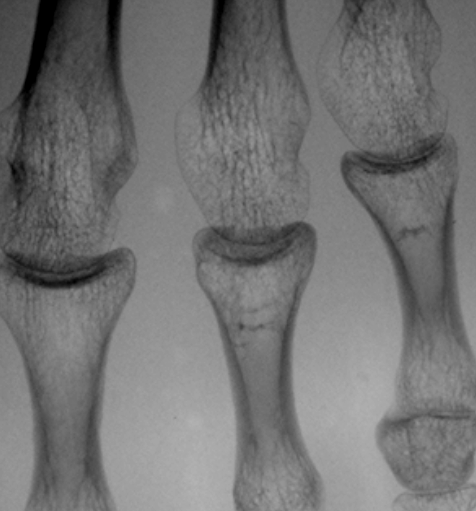

グリッド目除去は、縦方向の信号成分を

一部抜き去る処理であるため、縦方向の

骨梁の一部が消失してしまっている

ピクセル・アラインド・グリッド

(66.8本/cm,0.15mm間隔)

信号消失がまったくない